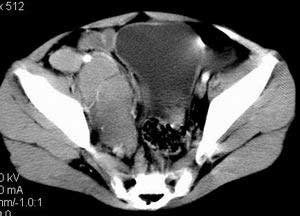

| 患者,男,9岁,因右下腹包块入院,血象不高,不规则发热,常超40度。 平扫: ![]() ![]() ![]() ![]() ![]() ![]() ![]() ![]() ![]() ![]() ![]() ![]() ![]() ![]() ![]() ![]() ![]() ![]() 增强: ![]() ![]() ![]() ![]() ![]() ![]() ![]() ![]() ![]() ![]() ![]() ![]() ![]() ![]() jiajie发言:骶椎右前区不规则软组织肿块,边缘光整,密度均匀,增强后均匀强化,右腹股沟区可见肿大淋巴结,临床有时发热,考虑淋巴瘤,儿童盆腔肿瘤应与神经母细胞瘤和横纹肌肉瘤鉴别。 longzhanghui发言:印象:盆腔右后壁不规则软组织肿块,并向前延伸.似为多个肿块融合,呈中等强化.初步考虑淋巴瘤. 听蝉观竹发言:右侧髂内、外组淋巴结肿大,从其形态和融合的情况看,同意大家意见-----考虑恶性病变,但是9岁男孩还要注意检查睾丸情况,有无隐睾? 常常类似情况是隐睾发生精原细胞瘤淋巴结转移,这个病例也要注意这一点!!! 广东凌发言:大家好,在这里我想说一下个人观点,我建议上传图片的同志能否辛苦一点就是把病史和图片都上传完整一点,比如这个病人的腹膜窗,并且这个病人的肠道的准备也是不怎么好,就从现有的质料看:病灶属于淋巴结肿大当无大的争议,有融合趋势,其内无坏死,边缘强化为主,故考虑:淋巴瘤!建议用腹膜窗看一下和肠道的关系! 阿圣发言:病灶属于淋巴结肿大当无大的争议,有融合趋势,其内无坏死,边缘强化为主,故考虑:淋巴瘤 结果是:淋巴瘤 病例来源:ct762。由宁静致远发布: http://www.radinet.com.cn/forum_view.asp?forum_id=4&view_id=2182 |